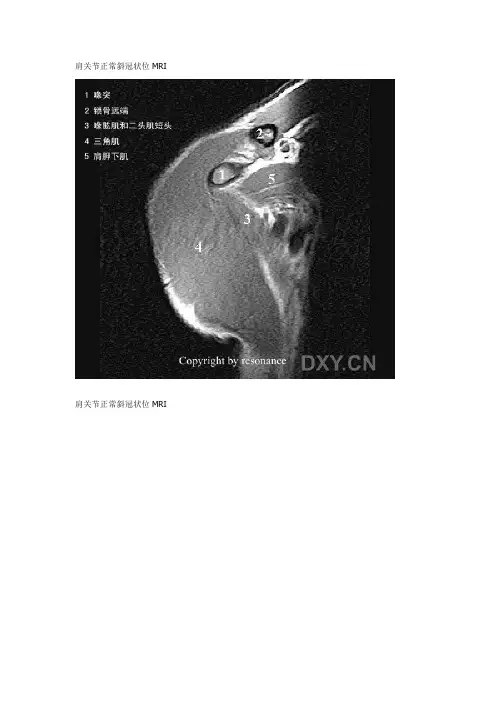

肩关节正常斜冠状位MRI